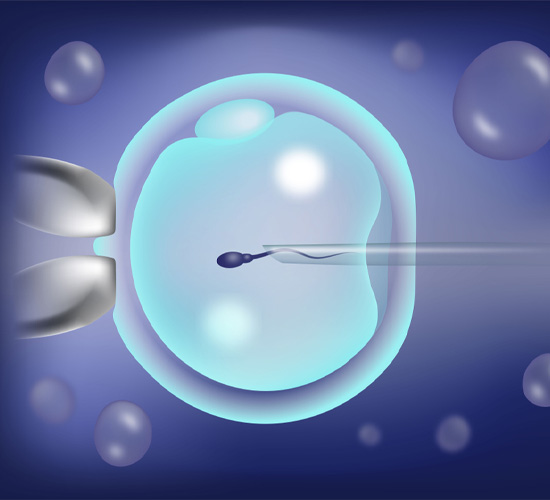

ICSI

ICSI is an advanced IVF technique where a single healthy sperm is directly injected into an egg, improving fertilization success rates.